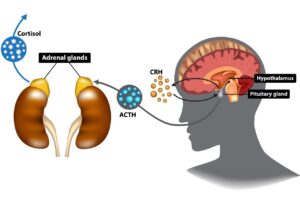

Η αξονική τομογραφία (CT) είναι ένα ιατρικό τεστ εικόνας που χρησιμοποιεί ακτίνες X για να δημιουργήσει λεπτές εικόνες των εσωτερικών μορφών και δομών του σώματος. Στον τομέα της ενδοκρινολογίας, ο ενδοκρινολόγος μπορεί να συστήσει την αξονική τομογραφία για διάφορους λόγους:

Η αξονική τομογραφία (CT) είναι ένα ιατρικό τεστ εικόνας που χρησιμοποιεί ακτίνες X για να δημιουργήσει λεπτές εικόνες των εσωτερικών μορφών και δομών του σώματος. Στον τομέα της ενδοκρινολογίας, ο ενδοκρινολόγος μπορεί να συστήσει την αξονική τομογραφία για διάφορους λόγους: